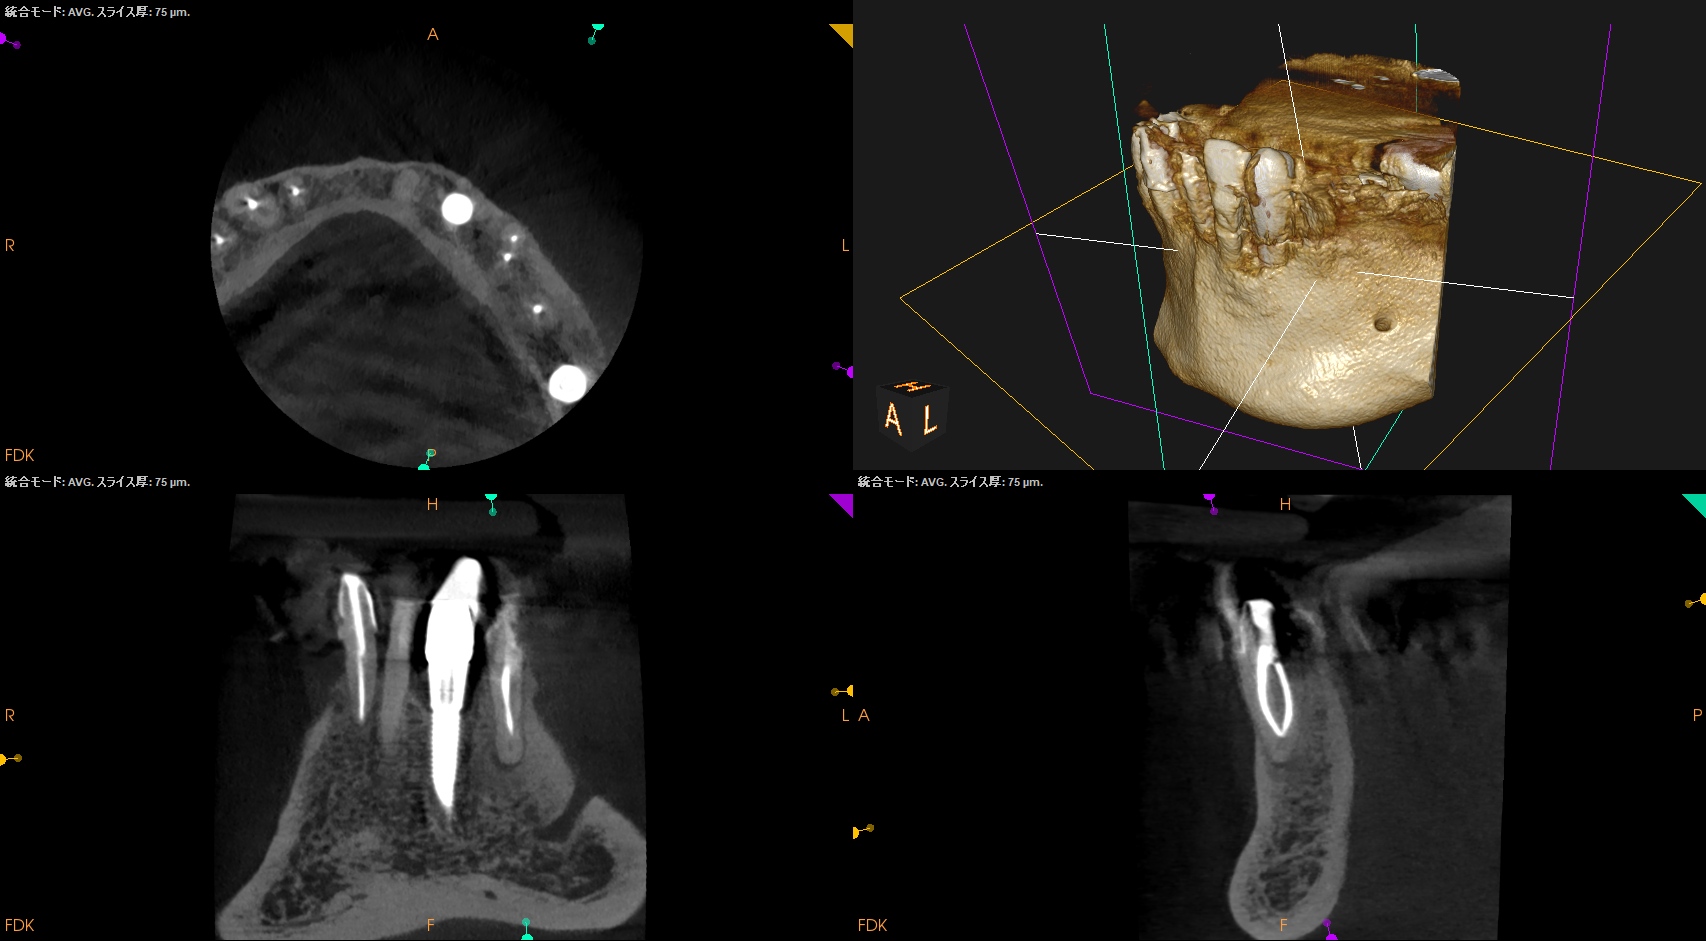

#21 Re-RCT 5M recall(2025.9.11)

穿通しなかったのに根尖病変は5ヶ月でほぼ消失した。

この現象に寄与したものはやはり、術前のコロナルリーケージだろう。そして再治療がそれを後押しした。そう。両方とも治療のKeyなのである。